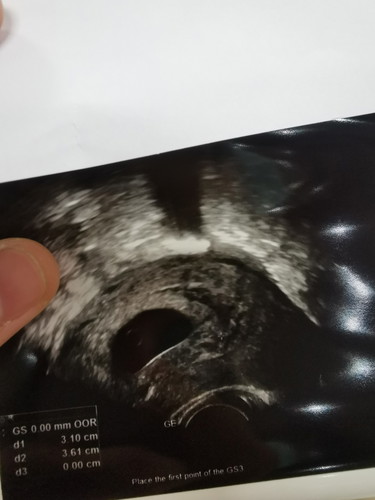

11สัปดาห์ แต่....

11สัปดาห์ แต่ยังไม่เจอตัวน้อง หมอบอกมีสิทธิ์เป็นท้องลม เลยขอโอกาสหมออีก1 อาทิด ถ้าอาทิดหน้ามาไม่เจอก็เตรียมตัวขูดมดลูก...วันนี้เลยรู้สึกแอบผิดหวังนิดๆ แต่ก็ลุ้นว่าอาทิตย์หน้าหวังว่าจะได้เจอน้อง